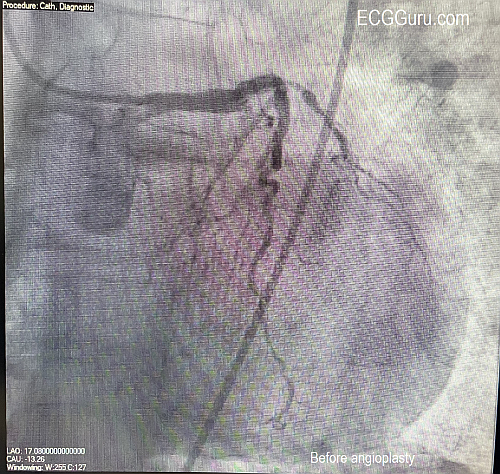

Instructors' Collection ECG: Acute Occlusive Myocardial Infarction With Cardiogenic Shock

The Patient:  67-year-old man complaining of chest pain radiating to his jaw, 10/10. He is short of breath and diaphoretic. We do not know his BP, just that it was low.  The patient states “no past medical history – never hospitalized”. He thought himself to be very healthy.  He was given aspirin 325 mg and transported to a full-service cardiac hospital as a “cardiac alert”.

The rhythm is atrial fibrillation with a rapid ventricular response (about 134/min.). The QRS width is .118 seconds (118 ms).  The frontal plane axis is slightly to the left, but WNL. The R wave progression mostly normal, but V4 is incongruous.  V2 and V3 have a tall R wave, possibly representing a pathological Q on the posterior side.  There are ST CHANGES in every lead. ST elevation is noted in III, aVF, aVR, V5 and V6, representing ischemia in the inferior wall. There is ST depression in all other leads, indicating widespread subendocardial ischemia and/or acute reciprocal depression.  Interesting that Lead II would normally be elevated when III and aVF are, but aVR is elevated, causing reciprocal ST depression in Lead II.  So, Lead II looks almost normal.

The pattern of ST elevation in aVR with widespread ST depression can indicate:

1)     Proximal occlusion of LAD or significant stenosis of Left Main artery.